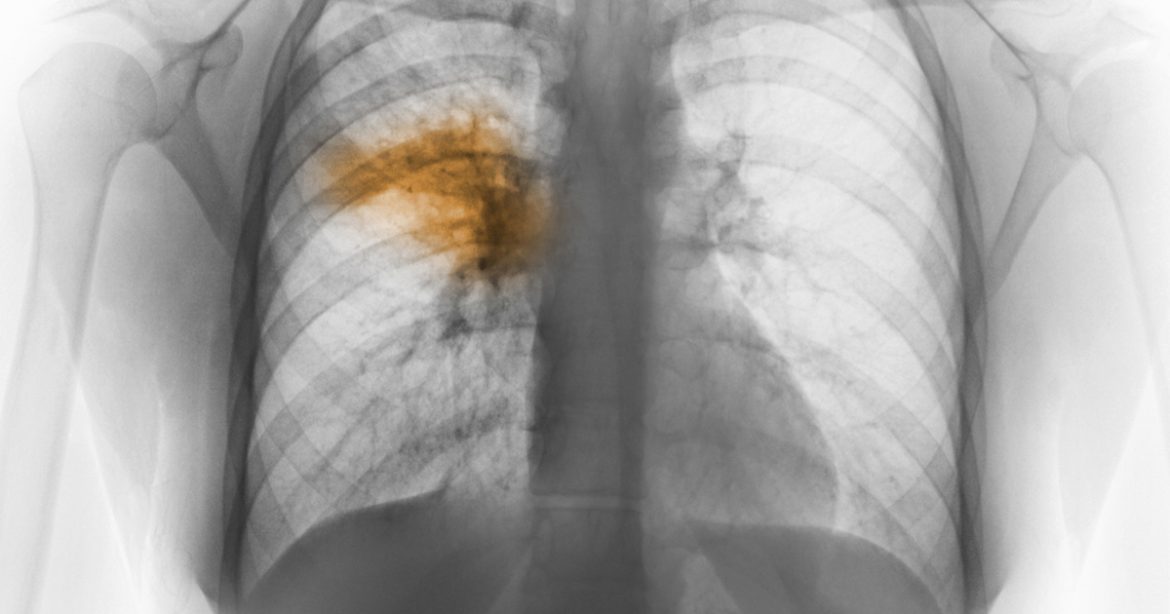

Pneumonia is a lung infection that inflames air sac in one or both the lungs . In this the air sac may fill with pus or fluid which cause cough , chills , fever and dysponea . There are various organisms that can cause pneumonia are bacteria , fungi or viruses .